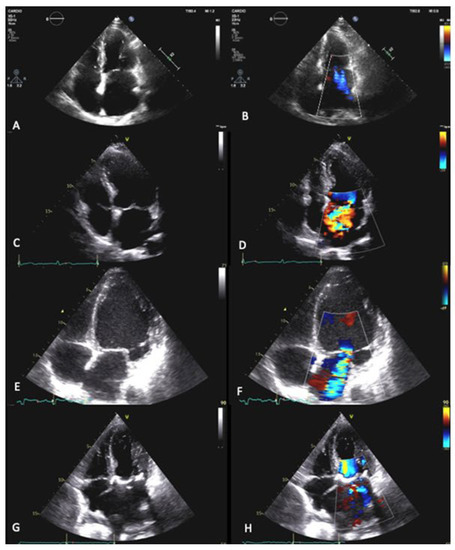

| Mitral Regurgitation | Primary: endocarditis, degenerative, papillary muscle rupture. Secondary: ischemic, dilated cardiomyopathy, atrial enlargement caused by AF | Type I: normal leaflet motion Type II: excessive leaflet motion Type III: restricted leaflet motion IIIa: leaflet motion restricted in both systole and diastole. IIIb: leaflet motion restricted in diastole | up to 10% of the general population; mitral valve prolapse: 3% of the general population. | Myxomatous degeneration (in the younger population), fibroelastic deficiency disease (in the elderly), LV dysfunction, LA dilatation |